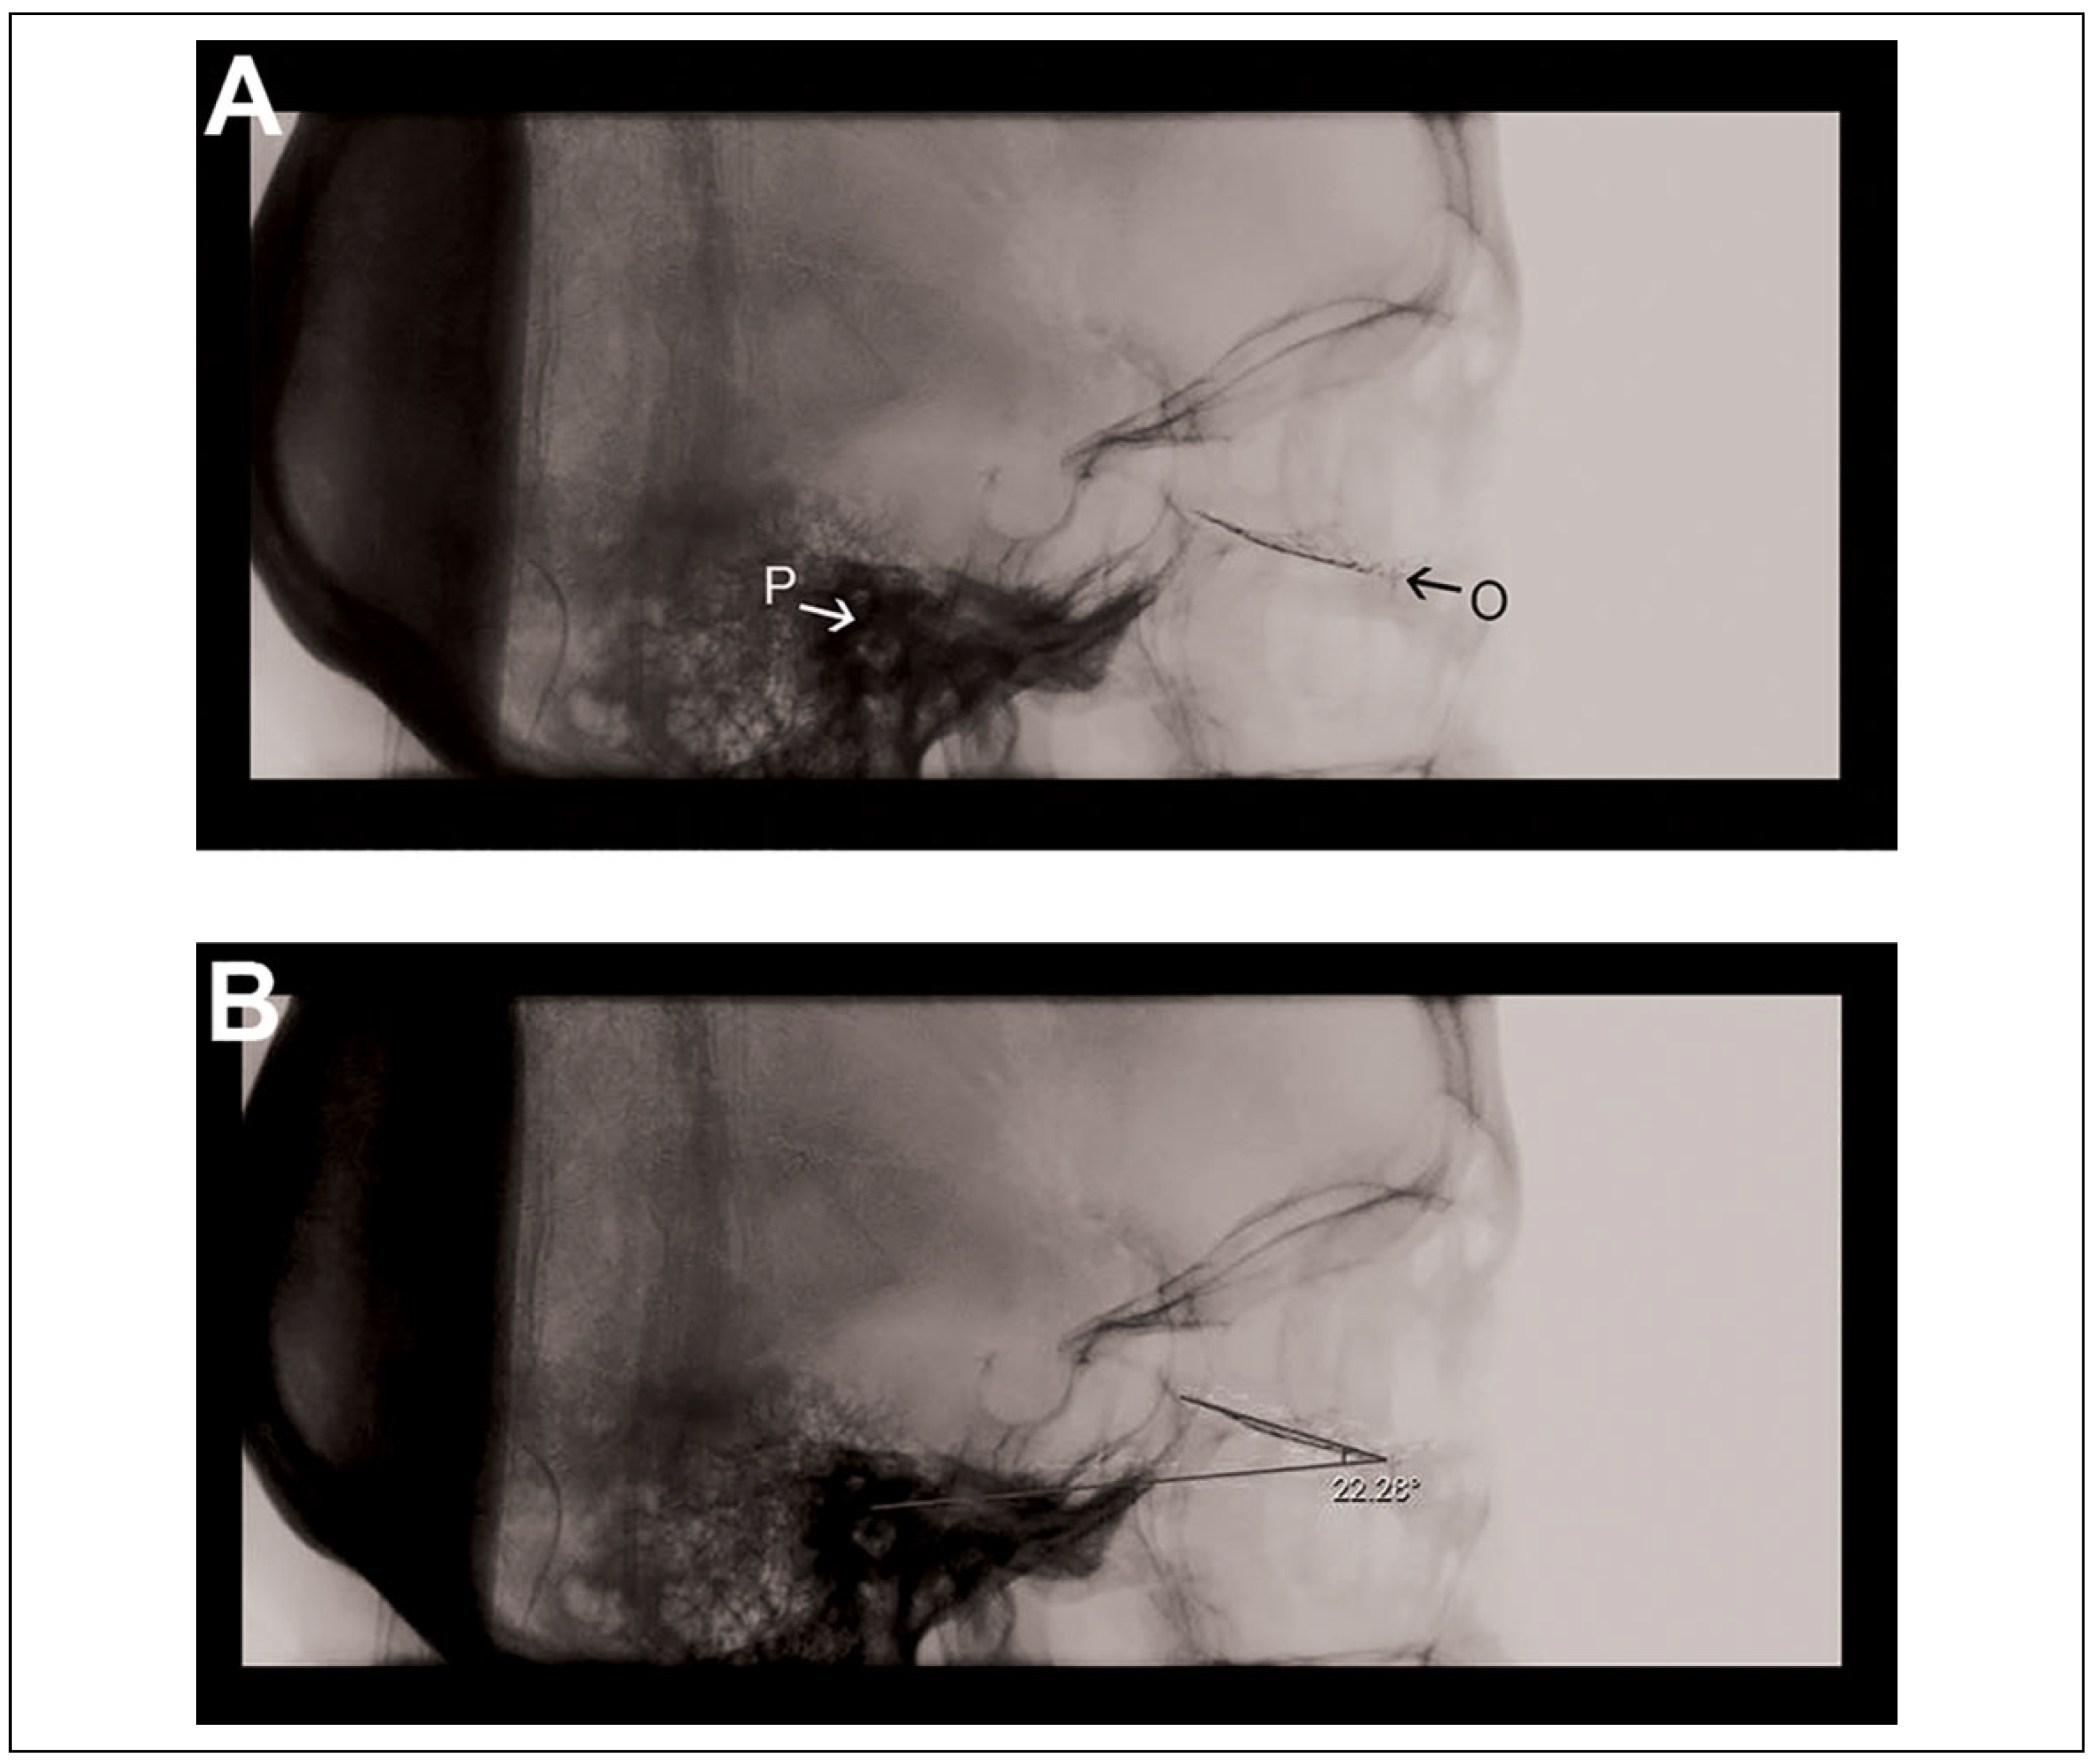

Based on clinical experience, most misplaced implants go through the fractured floor into the maxillary sinus. In that scenario, the angle (between the trough of the implant and the Frankfort horizontal plane) is decreased—and thus, if carefully assessed, would raise suspicions of inaccurate positioning of the implant. Based on our findings, this angle was fairly consistent among 14 different skull specimens, with a relatively tight standard deviation. It must be noted, however, that accurate measurement of this angle would require obtaining a true lateral radiograph, and adjusting the exposure to better differentiate the external acoustic meatus from the surrounding radio-dense petrous portion of the temporal bone. These tasks are not difficult to achieve as demonstrated on a sample intraoperative lateral radiograph of an actual patient in Figure 3. In our practice, we try to overcome the challenge of obtaining as true a lateral image as possible by making sure that landmarks such as the mastoid processes and orbits align. The external acoustic meatus can be identified on an intraoperative lateral radiograph as a distinct circular structure located anterior and cephalad to the mastoid air cells. Porion is the point at the superior most aspect of the meatus. Most imaging devices are equipped with software that allows for measurement of angles on the screen intraoperatively.

As an example from our institution, Figure 3 demonstrates a lateral scout taken before the final scan on the O-arm. This is a 53-year-old female with an orbital floor fracture who underwent repair with a titanium fan implant. The measured angle happens to be 22.3°, which is within 1 standard deviation from the measured mean on the dry skull specimens in this study.

Figure 3. Recent case of a 53-year-old female with an orbital floor fracture, who underwent repair with a titanium fan implant. (A) Lateral scout from intraoperative O-arm imaging. (B) The in vivo angle (22°) that the trough of the implant makes with the Frankfort horizontal plane. O indicates orbitale; P, porion.